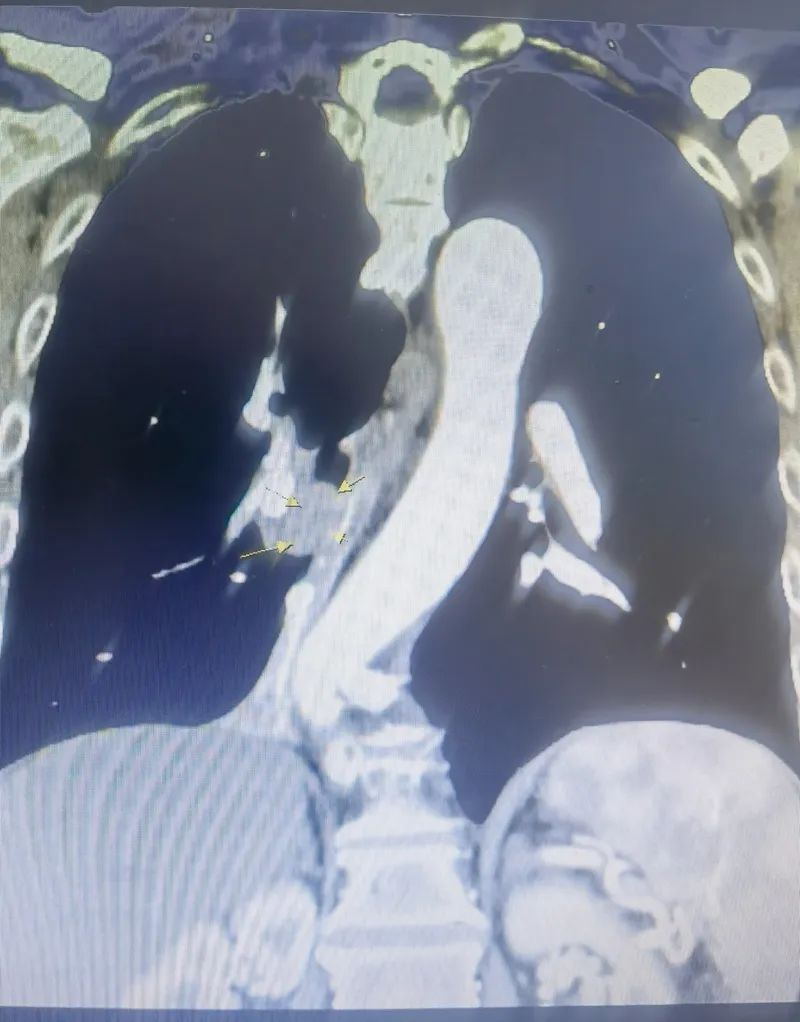

67岁的叶伯伯前来我院就诊,向医生表示已经反复咳嗽3周没有好转。入院后患者完善胸部增强CT检查示:右肺下叶支气管占位性病变,并右肺下叶肺不张。患者行支气管镜检查示:右中间支气管重度外压狭窄并粘膜浸润性改变,并行右中间支气管活检术,术后病理回报:(右中间支气管新生物活检)非小细胞性肺癌,形态考虑浸润性中分化鳞状细胞癌,免疫组化:CK5/6(+),P63(部分+),CK7(-),NapsinA(-),TTF-1(-),CD56(-),CgA(-),Ki-67(+,热点区约30%),结合免疫组化诊断:(右中间支气管新生物)浸润性中分化鳞状细胞癌。完善颅脑MRI、腹部彩超未见远处转移征象。术前临床分期:右中肺浸润性中分化鳞状细胞癌cT1NxM0 ,胸外科同时请了肿瘤科、麻醉科、呼吸内科多学科会诊评估手术风险,特别手术范围的确定,跟放射科沟通讨论,重建支气管影像沟通探讨,结合图片考虑中间支气管肿物跟中叶支气管开口距离太近,为保留中叶肿瘤残留可能性非常大,术前肺功能正常,完全可以耐受中下肺叶切除。讨论结果择期行胸腔镜下右侧中下肺叶切除术+纵隔淋巴结清扫术。

▲术前胸部增强CT检查